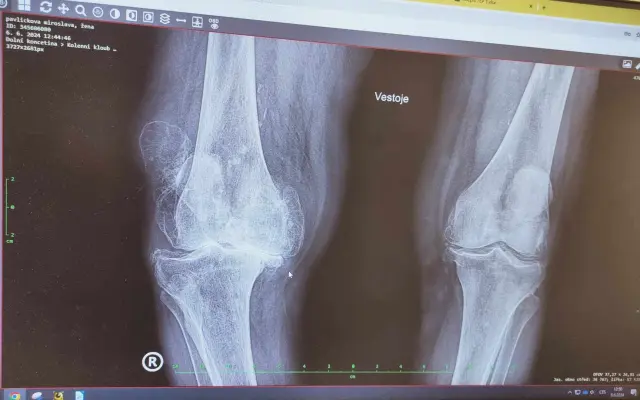

Pomoc bude směřovat na zajištění mobility více než 90leté babičky, která se po těžkém úraze a neúspěšné léčbě, v kombinaci s velmi vysokým stářím stala již zcela imobilní. V reálu je její koleno 2,5× větší než druhé (RTG snímek nezachytí) stav je už nezvratitelný, doživotní.